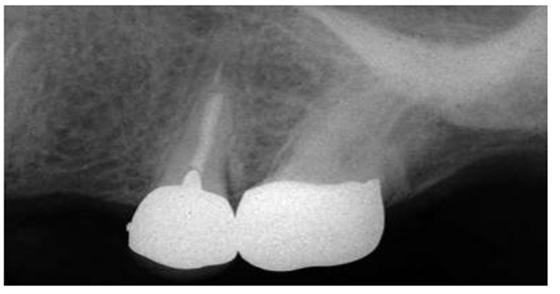

圖3:上頜第二前磨牙,牙根里非常短的樁

盡管短樁從未被提倡使用,但是研究發(fā)現(xiàn)經(jīng)常能在根尖片上觀察到短樁的存在(圖 3)。臨床上發(fā)現(xiàn)在327例樁修復(fù)當(dāng)中,僅僅有34%的樁長(zhǎng)度與冠上切-頸長(zhǎng)度相當(dāng),即冠與樁長(zhǎng)度的比例為1:1。一項(xiàng)研究曾對(duì)200例牙髓治療后的牙齒進(jìn)行評(píng)估,結(jié)果顯示僅僅14%的樁長(zhǎng)度為牙根長(zhǎng)度的2/3或者長(zhǎng)于牙根長(zhǎng)度的2/3。另外一項(xiàng)根尖片研究結(jié)果表明樁修復(fù)中,樁長(zhǎng)度為牙根長(zhǎng)度的2/3或者3/4的比例僅占5%。當(dāng)臨床上應(yīng)用短樁修復(fù)時(shí),由于高應(yīng)力的原因,牙根常常會(huì)發(fā)生折斷,反之,增加樁的長(zhǎng)度能夠提高牙根的抗折能力。